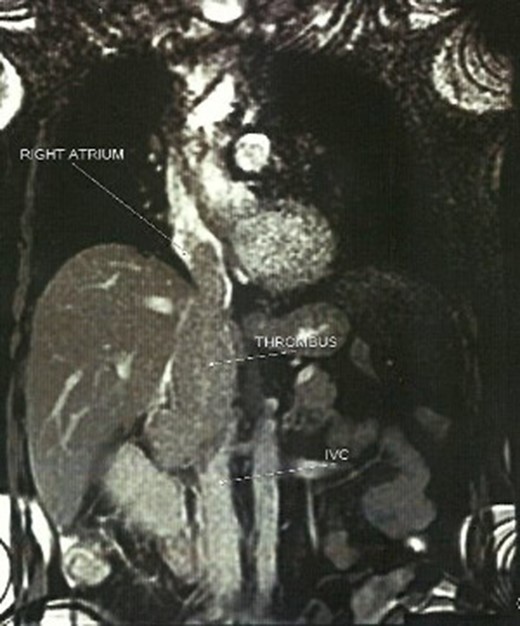

A 66-year-old male, former smoker with a history of hypertension, chronic obstructive pulmonary disease and glaucoma was delivered to the emergency department after a presyncope episode. The patient mentioned episodes of diarrheic melaenas over the last 2 weeks, a progressively worsening dysthymia over the last 2 months and a constant pain of the right lower lumbar region of more than five months that was diagnosed as a hernia. ECG showed sinus rhythm with frequent atrial ectopics. The clinical examination was without special findings and malaena was not clinically confirmed. Vital signs were measured within normal limits. Laboratories revealed anemia (Hct 30.4%, Hb 9.8%), mild elevation of liver enzymes (gGT 197, ALP 186) and CRP (14.1 mg%). Cardiac markers and fecal occult blood test were negative. An abdominal ultrasound revealed a heterogenous mass (6.8 × 6.7 cm2) on the upper pole of the right kidney and a tumor thrombus extending to the IVC. The CT scan of the abdomen and the thorax confirmed the diagnosis of renal mass with cavoatrial tumor thrombus. Pre-surgical staging with MRI and angiography revealed no other sites of pathology or metastasis (Fig. 1).